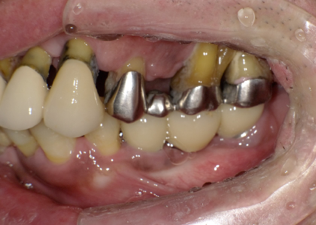

前歯に連結固定した差し歯が入っています。おそらく奥歯がなりなり、噛めなくなるので、前歯でしっかり噛めるように連結固定したのだと思いますが・・

治療前の写真です。前歯がぐらぐらになっています

奥歯がなくなり、前歯ばかりで噛んでいるとフレアーアウトといって前歯がどんどん前に傾いて出てきます。